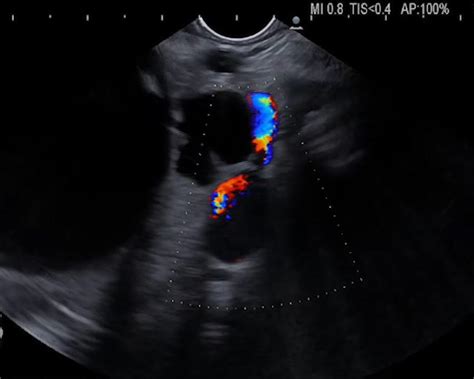

When it comes to diagnosis and treatment options for pancreatic cysts and pseudocysts , there are several approaches that doctors use. The goal is to accurately identify the type of lesion, assess its risk, and determine the best course of action for each individual patient. Diagnostic techniques play a crucial role in differentiating between cysts and pseudocysts. Imaging tests such as CT scans, MRI, and endoscopic ultrasound (EUS) are commonly used to visualize the pancreas and identify any abnormalities. These tests can help doctors determine the size, location, and characteristics of the lesion. EUS is particularly useful because it allows for a close-up view of the pancreas and enables doctors to obtain tissue samples for further analysis. Cyst fluid analysis is another important diagnostic tool. During EUS, a needle can be inserted into the cyst or pseudocyst to collect fluid. This fluid is then sent to a laboratory for analysis, which can help determine the type of lesion and assess its risk of malignancy. Fluid analysis can include measuring levels of amylase, lipase, CEA, and other markers. Treatment options vary depending on the type of lesion, its size, symptoms, and the overall health of the patient. Small, asymptomatic cysts might only require monitoring with periodic imaging. This approach is often used for cysts that are unlikely to cause problems or become cancerous. Larger cysts or those that are causing symptoms might need to be drained. Drainage can be done in several ways, including surgically, endoscopically, or percutaneously. Surgical drainage involves creating an opening between the cyst and the stomach or small intestine, allowing the fluid to drain into the digestive system. Endoscopic drainage involves using an endoscope to create a similar opening. Percutaneous drainage involves inserting a needle through the skin and into the cyst to drain the fluid. Surgical removal is often recommended for cysts with a higher risk of becoming cancerous. This involves removing the cyst and any surrounding tissue to prevent the spread of cancer. Surgical removal can be done through open surgery or minimally invasive surgery, depending on the size and location of the cyst. For pseudocysts, treatment typically involves addressing the underlying cause of the pancreatitis. This might include removing gallstones, stopping alcohol abuse, or managing other medical conditions. Drainage is often necessary for pseudocysts that are causing symptoms or complications. The same drainage techniques used for cysts can also be used for pseudocysts. In some cases, a pseudocyst can resolve on its own without any intervention. However, if it’s causing significant symptoms or complications, drainage is usually necessary. Overall, the diagnosis and treatment of pancreatic cysts and pseudocysts require a multidisciplinary approach involving gastroenterologists, surgeons, radiologists, and other healthcare professionals. The goal is to provide the best possible care for each patient based on their individual circumstances.